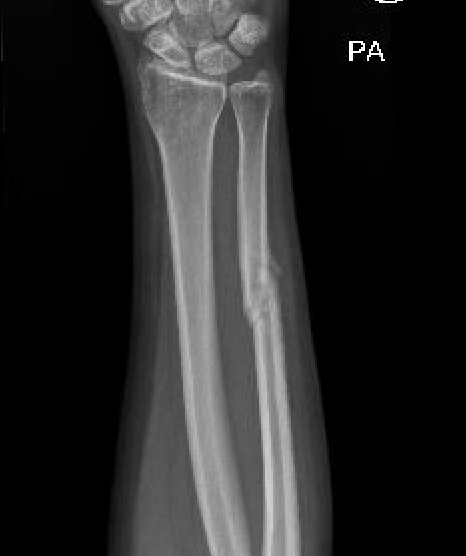

Results

Long arm cast not necessary

Van Leemput et al Acta Orthop Belg 2007

- 102 isolated ulna fractures

- long arm cast v short arm cast v bandage

- no difference in union rates

Increased nonunion rates with midshaft versus distal fractures

Henry et al J Hand Surg Am 2023

- 95 isolated ulna fractures

- union rate nonoperative: 91%

- union rate operative: 97%

- increased nonunion with midshaft (30%) versus distal 1/3 fractures (2%)